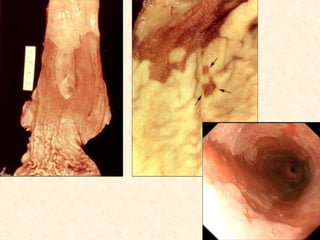

Esôfago, carcinoma epidermóide

Padrão de crescimento

 Polipóide          60%

 Ulcerante          25%

 Infiltrante        15%

 (misto)

Clínica

 Disfagia (após diminuição 70% da luz)

 Odinofagia

 Halitose

 Perda de peso

 Aspiração de alimentos

 Fístula

 Rouquidão

Esôfago, carcinoma epidermóide Padrão de crescimento  Polipóide 60%  Ulcerante 25%  Infiltrante 15%  (misto)

• 57.

Esôfago, carcinoma epidermóide Clínica  Disfagia (após diminuição 70% da luz)  Odinofagia  Halitose  Perda de peso  Aspiração de alimentos  Fístula  Rouquidão